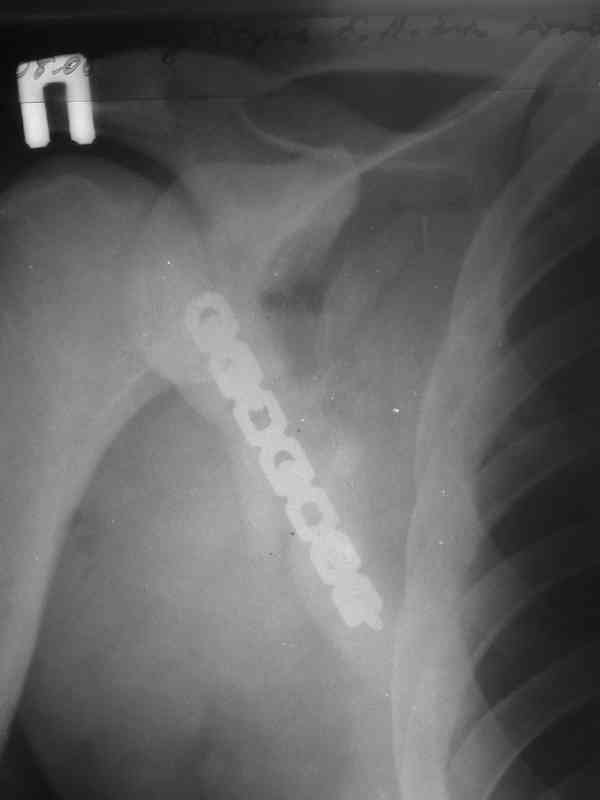

Re: Перелом лопатки, ключицы, ребер

Мы в таких случаях оперируем в 2-а этапа:

1. Стабилизация грудной клетки(фиксируем ребра по одной из линий рекон. LCP)

2. Остеосинтез лопатки из заднего доступа(рекон.LCP, LC-LCP 3,5мм, Т-обр.LCP 3,5мм); ключицу стандартно